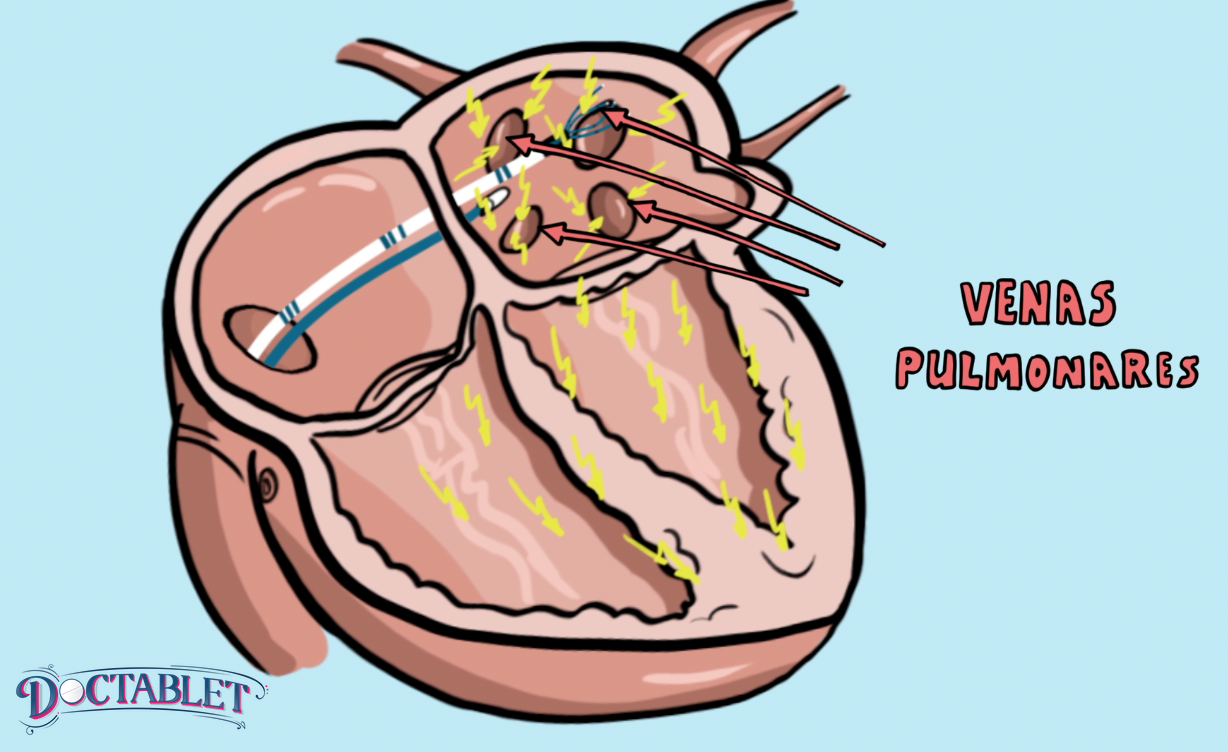

Con una ablación, los médicos pueden dirigirse a la raíz del problema que causa la FA. Lo hacen rastreando las descargas eléctricas anormales que causan el ritmo cardíaco irregular y encontrando las partes del corazón en donde ocurren. Hasta el 85% de estas descargas ocurren en la parte del corazón que recibe sangre de los pulmones: las venas pulmonares. Una vez que encuentran estas zonas provocantes, los médicos entran al corazón usando un acceso mínimamente invasivo. Cuando están dentro de la aurícula, enfocan y atacan estas zonas sensibles, dejando las partes normales intactas.